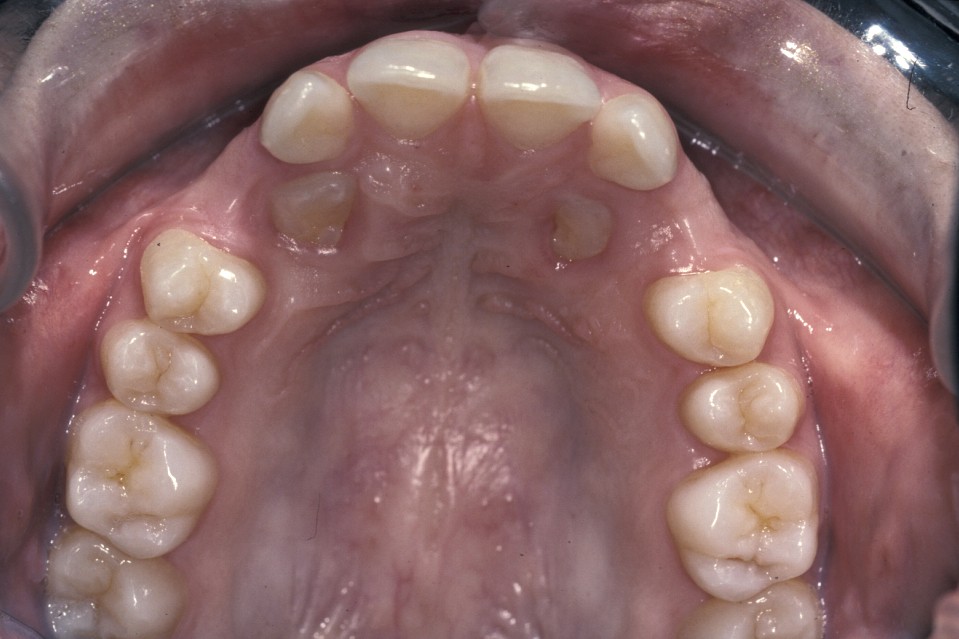

- Palatally placed canines - open eruption can also be used in the treatment of palatally ectopic canines, especially when they are relatively superficial. As the palatal mucosa is all keratinized, the problem of ensuring that the tooth erupts through here is to ensure adequate crown is exposed to ensure that there is no chance of the crown becoming recovered during the healing phase. If necessary, a bracket can be attached at the time of surgery in the same manner as for closed eruption. Care must be taken to ensure that the cementum is not damaged during surgery and that keratinized mucosa is left overlying the cementum - enamel junction. Interestingly even if large areas of bone are left denuded after surgery healing is usually excellent and uneventful. Packs can be placed over the exposed tooth to aid haemostasis, comfort and to prevent the tooth becoming covered again. This has historically involved the placing of ribbon gauze soaked in varnish and secured in place with mattress type sutures. Periodontal dressing can also be used. The pack should be removed after 7 to 14 days, from when on vigorous oral hygiene measures are vital to encourage healing, prevent gingival overgrowth and encourage eruption (Figure 19 and Figure 20).